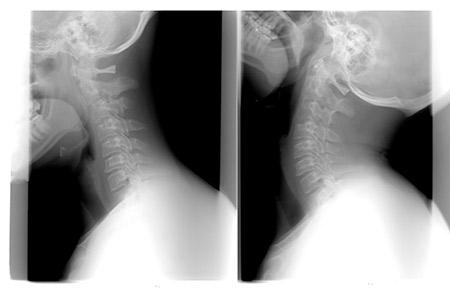

Ante el Whiplash o latigazo cervical la Kinesiología es de gran ayuda. A través de los test musculares podremos realizar pruebas dinámicas para valorar alguna respuesta que podamos utilizar para apoyar la recuperación de esta lesión típica en accidentes de tráfico, sobre todo cuando estamos parados.

Cuando sufrimos un golpe por detrás en nuestro vehículo, en semáforos, atascos, circunstancias de tráfico…, el impacto genera un desplazamiento brusco de la cabeza. Además, al estar sujetos por el cinturón, se bloquean los músculos del cuello y se produce ese latigazo cervical que tantos problemas de salud genera.

Lo golpes secos en circulación por detrás del vehículo (colisión por alcance) llevan asociados una serie de problemas musculares que con Kinesiología se pueden tratar. Tras una colisión de estas características, no solo se genera ese Whiplash, sino que también ante el susto la boca se tiende a abrir, lo que afecta a nuestra ATM, la articulación temporo mandibular. A su vez, el golpe hace que nos aferremos al volante con tensión y esto puede implicar los hombros, codos y muñecas. Pero también, muchas veces, se pisa fuerte el freno para evitar un mayor desplazamiento, forzando así la cadera, la rodilla y el tobillo.

Muchas personas afectadas por este tipo de accidente sufren unos días de dolores en el cuello. Por este motivo se coloca un collarín durante un tiempo, pero cuando se pasa el dolor del cuello se puede sentir dolor lumbar o en las extremidades superiores o inferiores.

Como consecuencia del golpe seco suele producirse dolor de cabeza, hombros, entumecimiento en brazos o manos, mareos, alteración del suelo, rigidez en el cuello, dolor lumbar, problemas en las mandíbulas, alergias, cambios emocionales, alteraciones en la voz, ciática, problemas menstruales, problemas digestivos, inestabilidad, túnel carpiano… La Kinesiología en este tipo de accidentes en los que todo el cuerpo se pone en tensión y alerta, realiza con los tests musculares pruebas dinámicas para valorar si existe alguna respuesta que podamos utilizar para apoyar en la recuperación. Nos ofrece una visión global muy útil para el terapeuta y para la recuperación del paciente.

Es importante destacar que en estos tests también evaluamos los tejidos blandos (ligamentos, discos y músculos) que no salen en las pruebas de RX. La debilidad de éstos puede crear un dolor por compensación.